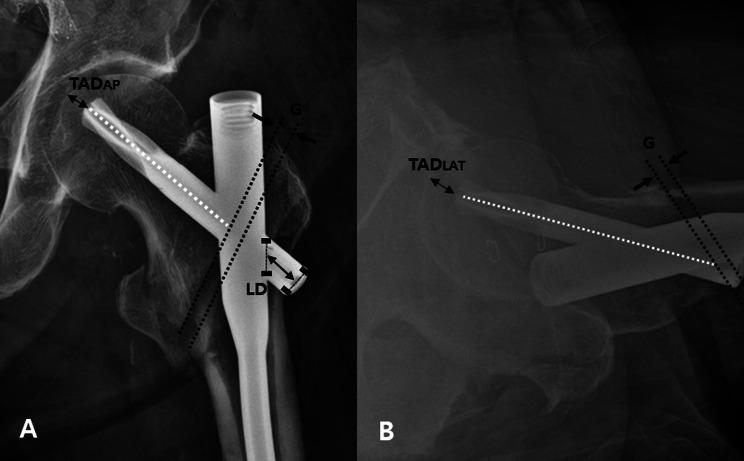

The average time to full weight-bearing was 8.44 ± 0.82 weeks (mean ± standard deviation) and to return to normal activities was 18.05 ± 0.89 weeks. The Harris Hip Score was 78.64 ± 1.03 at 12 months; all patients resumed independent walking at the final follow-up. The average fracture union time was 21.49 ± 1.75 weeks. In seven cases with a fracture gap at the time of breakage, significant change was observed in the tip-apex distance (P = 0.016) or lateral extension of the proximal femoral nail antirotation blade (P = 0.005) between the immediate post-surgery and final follow-up results, with the gap healing radiographically at 21.50 ± 1.65 weeks.

完全负重的平均时间为8.44±0.82周(均值±标准差),恢复正常活动的平均时间为18.05±0.89周。12个月时Harris髋关节评分78.64±1.03;所有患者在末次随访时均恢复独立行走。骨折平均愈合时间为21.49±1.75周。在7例断裂时存在骨折间隙的病例中,术后即刻与末次随访结果之间,尖顶距(P=0.016)或股骨近端抗旋髓内钉刀片的外侧延伸(P=0.005)有显著变化,骨折间隙在21.50±1.65周时影像学愈合。